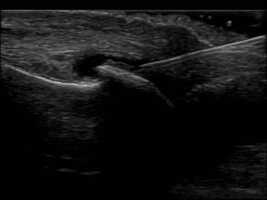

In plane ultrasound guided injection technique of the dorsal recess of the 1st MTPJ.